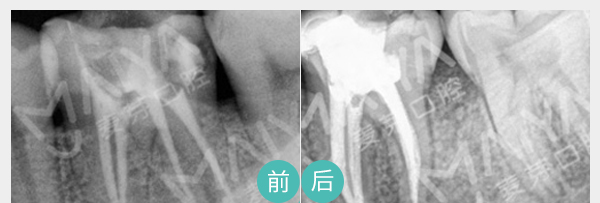

有助于医生判断病情、

并跟踪治疗效果